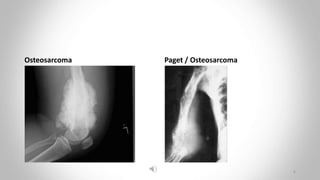

Osteosarcoma (osteogenic sarcoma)

• Mainly in the 5–20-year-old age group.

• Also seen in the elderly following malignant change in paget’s disease.

• Often arises in a metaphysis.

• Most commonly around the knee.

• Bone destruction

• New bone formation, and typically spiculated periosteal reaction

Is present, the so-called ‘sunray appearance’

• Elevate the periosteum to form a codman’s triangle

Osteosarcoma Paget / Osteosarcoma